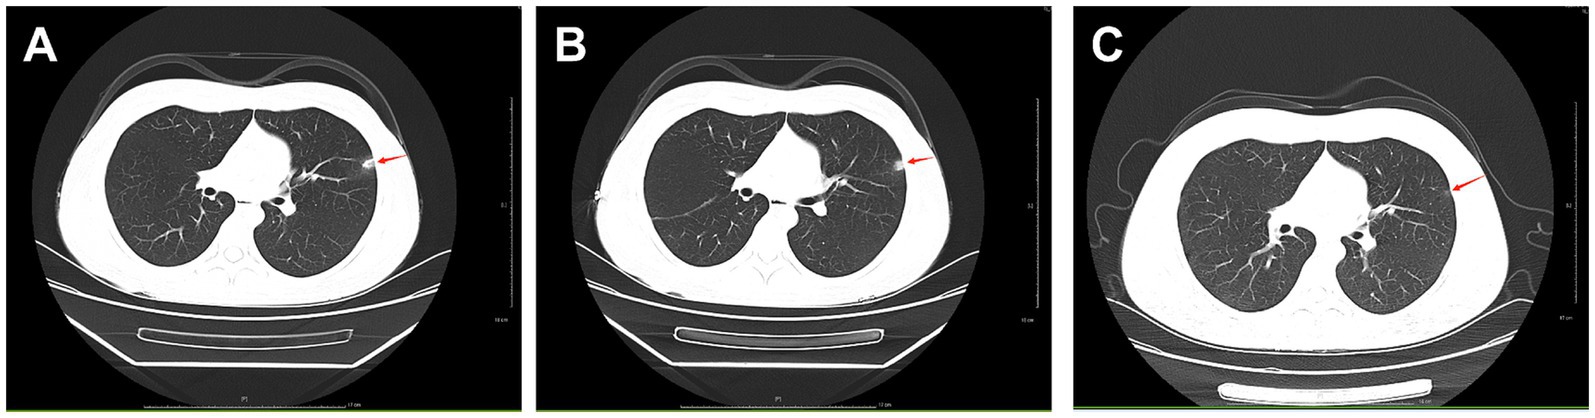

Six months ago, the patient developed menstrual chest tightness, chest pain, dyspnoea, cough with a small amount of bloody sputum, about 3–5 mL/d. There were no symptoms of fever, night sweats, fatigue, weight loss, etc., and the PPD test was negative at the outpatient clinic. Vaginal ultrasound suggested adenomyosis with fibroids. Lung CT: Lung infection is possible. Anti-infective treatment was given with poor results. Later, several follow-up CT scans showed periodic enlargement and shrinkage of the lung lesions. Combined with the patient’s medical history and imaging findings, thoracic endometriosis syndrome was considered. Goserelin extended-release implant (trade name: Norethindr 3.6 mg) was given subcutaneously from 24 September 2020 (1 time/1 month, a total of 6 times) until 22 March 2021, combined with tibolone tablets 2.5 mg orally, and then denogestrel 2 mg qd for maintenance (March 2021-present). During this period, the patient came to the hospital regularly for follow-up examinations of coagulation routine, blood routine (see Table 3), liver and kidney functions (see Table 4), sex hormones (see Table 5), and breast ultrasound, all of which showed no significant abnormalities. There was no progression of lesions on lung CT (see Figure 2). During the medication period, the patient had no symptoms of coughing up blood and no menstrual flow. She had occasional hot flushes, excessive sweating, irritability and insomnia. A perimenopausal syndrome was considered and she was given Shannon granules, which greatly relieved her symptoms. There were no symptoms of dizziness, breast discomfort, depression, acne, osteoarthralgia, etc. during the medication (follow-up to date has been approximately 5 years).

Figure 2. A: lung CT (plain scan + enhancement, 2021-01-06): fibrous streaks seen in the middle lobe of the right lung and the lower lingual segment of the upper lobe of the left lung, with well defined borders, and enhancement partially visible on enhanced scan. B: lung CT (plain + enhanced, 2022-08-30): striated hyperdense shadows seen in the upper and middle lobes of the right lung and the lower lobe of the left lung, enhancement did not show significant enhancement. C: CT lungs (plain scan, 2023-10-10): striated hyperdense shadows seen in the upper and middle lobes of the right lung and the lower lobe of the left.